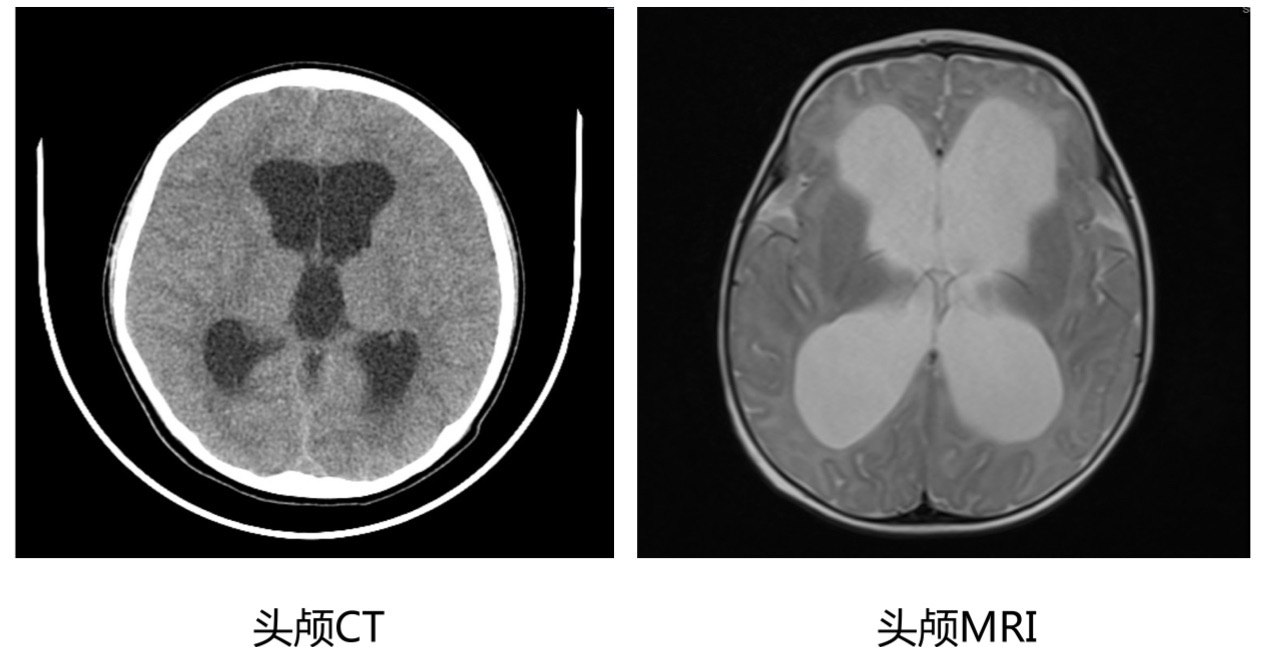

3. 头颅CT或者头颅MRI:对于疑似脑积水的年龄较大的婴儿和儿童,应该进行头颅CT或者头颅MRI检查,除了评估脑积水的程度,还可以发现结构异常或者肿瘤等后天因素。

脑积水头颅CT和MRI的影像学表现